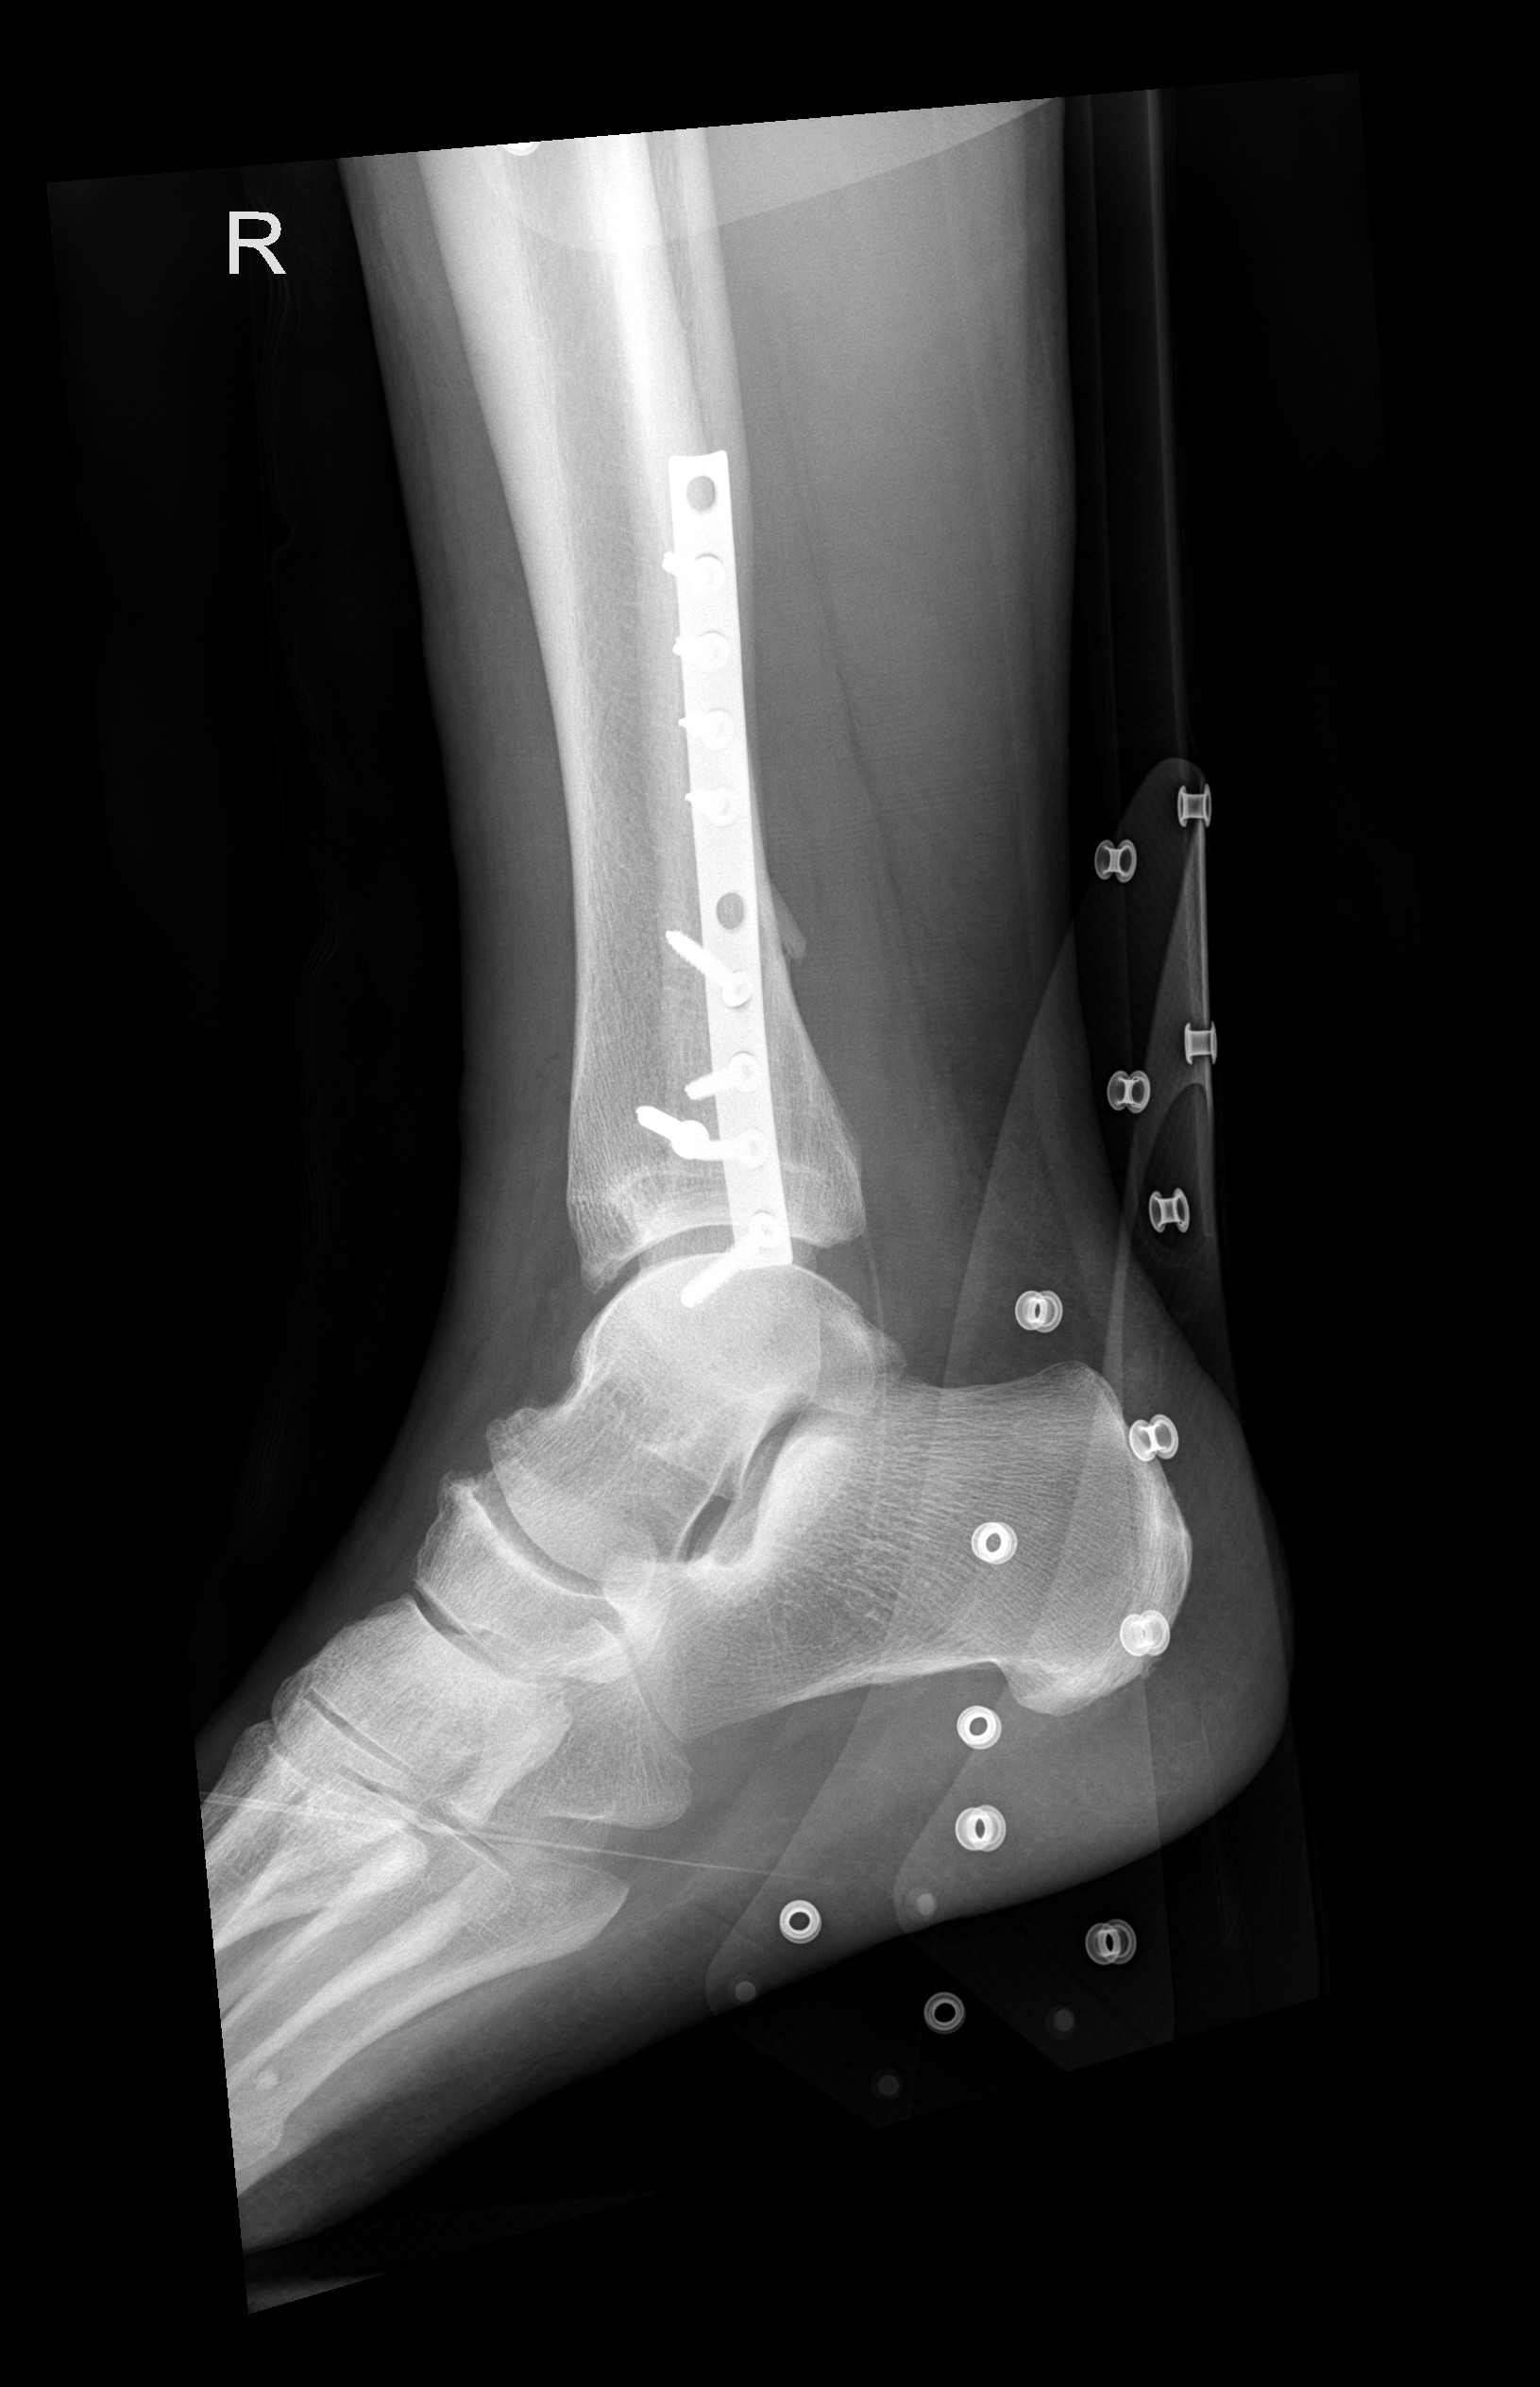

In der Notaufnahme konnte ich dann erstmals mein Bein frei machen. Die Besatzung der REGA verabschiedete sich und schon bald bestätigten die Röntenbilder einen Bruch des Wadenbeins. Ich war mindestens etwas erleichtert, dass es kein siebenfacher Trümmerbruch war wie letztes Mal, aber in dem Fall ist das eher Zufriedenheit auf tiefem Niveau.

Die lange Schraube stabilisiert Schien- und Wadenbein, bis der genähte Syndesmosebandriss ausgeheilt ist. Eine Syndesmose ist eine bandartige Verbindung zwischen zwei Knochen, die aus straffem Bindegewebe besteht und als «unechtes Gelenk» gilt; sie stabilisiert vor allem das obere Sprunggelenk zwischen Schien- (Tibia) und Wadenbein (Fibula) und ermöglicht eine begrenzte Bewegung, wobei eine Verletzung zu Instabilität führt und oft eine operative Stabilisierung erfordert. Diese Stabilisierungschraube muss in 6 Wochen wieder raus, danach ist das Gerüst wieder voll belastbar.

Die Schiene kann in frühestens 9 Monaten herausoperiert werden, ich werde den Termin dann aber eher im November vereinbaren.